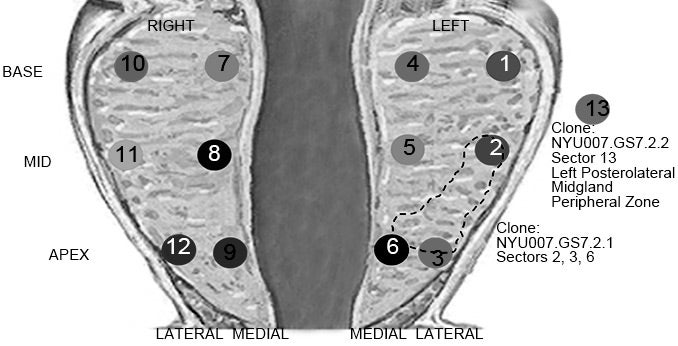

The newly tested method, devised by CSHL Professor Michael Wigler and Associate Professor Alexander Krasnitz, draws the raw material for further analysis from the standard pre-surgical biopsy. The team sequences the genomes of several hundred single cells sampled from each patient’s diagnostic biopsy cores. They search for certain patterns—for the presence of DNA disturbances called copy-number variations (CNVs). Using computational methods to compare CNV patterns, the team looks for cells whose CNV profiles harbor the same irregularities. This is a sign of clonality. Cancerous tumors are composed of clonal cells—genetically aberrant cells that derive from a single wayward ancestor.

The CSHL method assigns a number to each set of biopsy cores, based on how many of the cores contain clonal cells, how many clonal cells each contains, and how far such cells have dispersed within the prostate. In tests on 8 patients based on collaborations with NYU and Cornell University medical centers, the CSHL testing method yielded assessments of tumors that more closely matched the verdict of post-surgical pathological analysis (which reveal actual pathology) than the corresponding pre-surgical predictive biopsies, according to first author Joan Alexander, M.D.